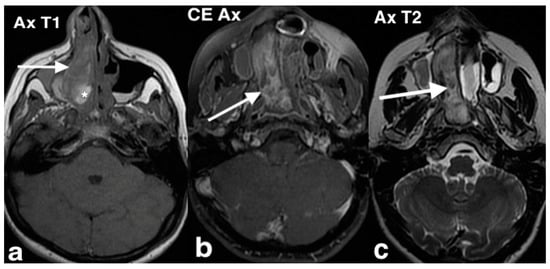

3.2.10. Sinonasal Tract Angiofibroma